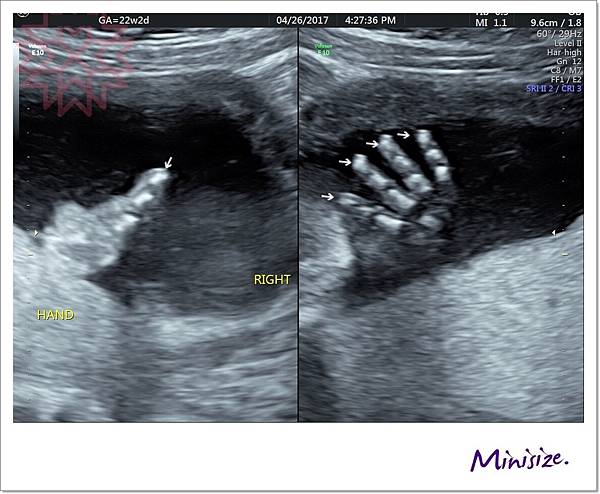

手

剛好我的寶寶手手有摺起來

技術師用兩種不同角度拍照

檢查時會細數1、2、3、4、5 五支手指頭

下兩張左圖都是大拇指 右圖是其餘四指

手指看起來很修長應該是遺傳麻麻

右手

左手